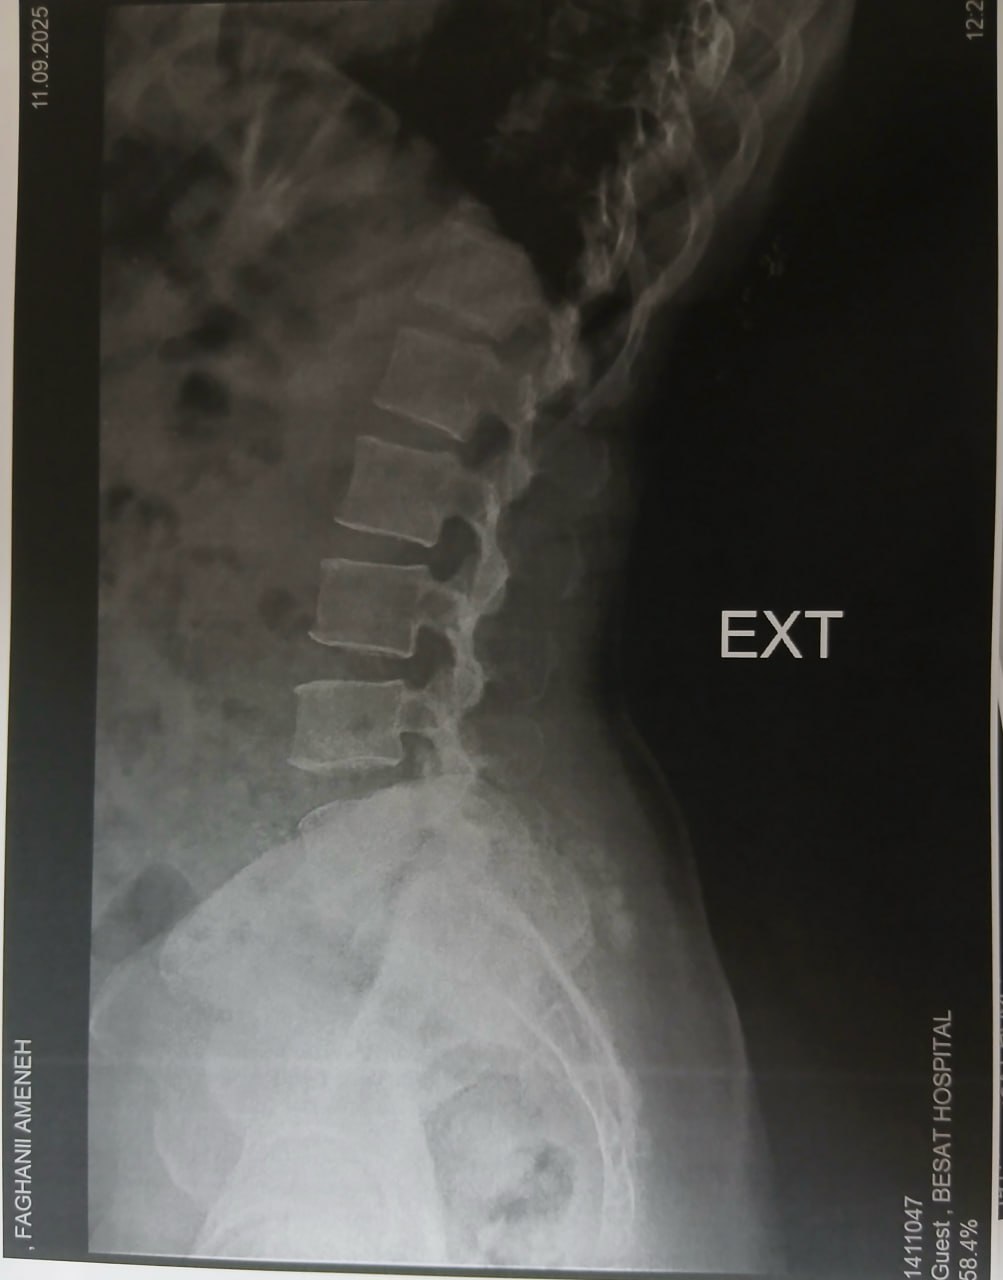

(تصویر مربوط به این مراجعه نیست) Other:

(تصویر مربوط به این مراجعه نیست) Other:

(تصویر مربوط به این مراجعه نیست) Other:

(تصویر مربوط به این مراجعه نیست) Other: